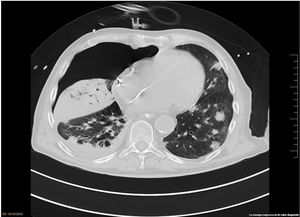

The chest-CT scan showed an extensive right lung consolidation and bilateral nodular consolidative foci (Fig. 1). Empiric liposomal amphotericin B was added to improve fungal coverage. A bronchoalveolar lavage (BAL) was performed. Multiplex PCR for respiratory viruses and bacteria (influenza, respiratory syncytial virus, CMV, adenovirus, coronavirus, rhinovirus, Legionella, Mycoplasma, Chlamydia, Escherichia coli, Klebsiella, Moraxella, Serratia, S. aureus, S. pneumoniae) were negative. No acid-fast bacilli were observed in the auramine stain. On direct examination with Gram and Calcofluor stain of the BAL a microorganism compatible with C. posadasii was found, and later confirmed on cultures (Figs. 2 and 3). The patient continued to require high oxygen requirements and eventually developed multiorgan failure. Nine days after admission the patient died. On the necropsy, spherules full of endospores were found within the pulmonary parenchyma, confirming an invasive fungal infection (Fig. 4).